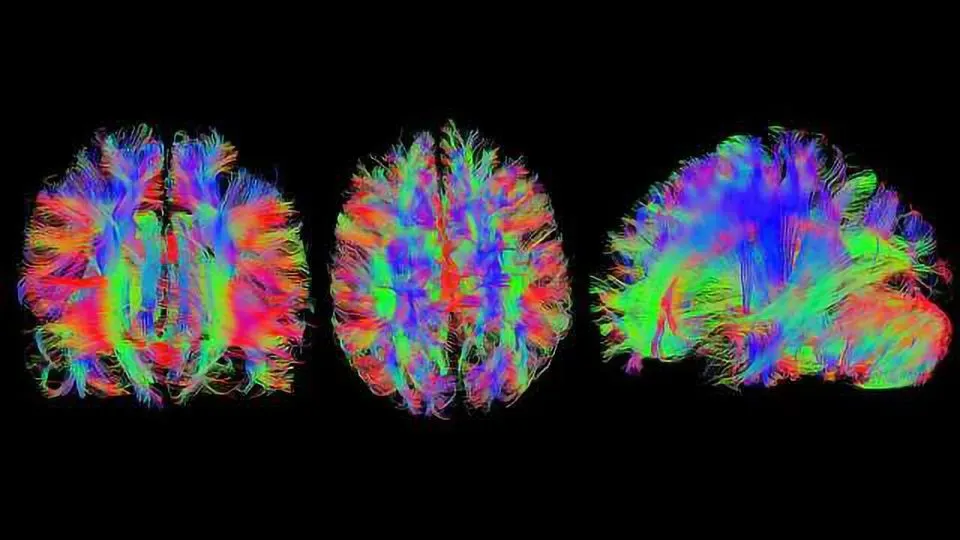

I'm 4th year at Northeastern University majoring in Data Science and Behavioral Neuroscience. I'm incredibly interested in the intersection of technology and healthcare, especially in how we can apply advanced data science techniques to understand and treat neurodegeneration.